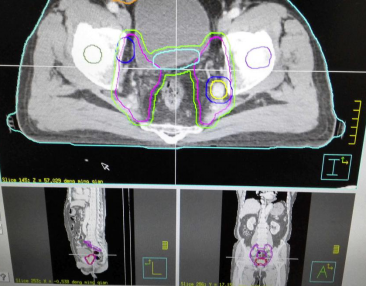

通过更新放射治疗计划系统,把原来的三维适形放疗(three dimensional conformal radiation therapy 3D-CRT)计划系统更新为目前主流的调强放疗(intensity modulated radiation therapy,IMRT)计划系统,从而完成放射治疗模式的升级。利用更新后的计划系统,放疗中心不仅可以进行三维适形放疗,而且可以进行调强放疗。

调强放疗是通过精确的定位、精确的计划、精确的照射最大限度地保证将放射线的剂量集中到肿瘤内,使癌症病灶组织得到高强度的照射,同时又保护了周围正常组织,治疗副作用明显减少。与普通放疗相比,调强放疗具有以下优点:①极大限度减少放疗靶区周围正常组织的放射剂量,降低放疗的副作用;②提高单次放疗剂量和放疗总剂量,提高肿瘤的局控率和生存率;③能够给予同一治疗靶区内不同放疗剂量,实现治疗靶区剂量梯度;④能够在一次放疗中同时照射多个放疗靶区。